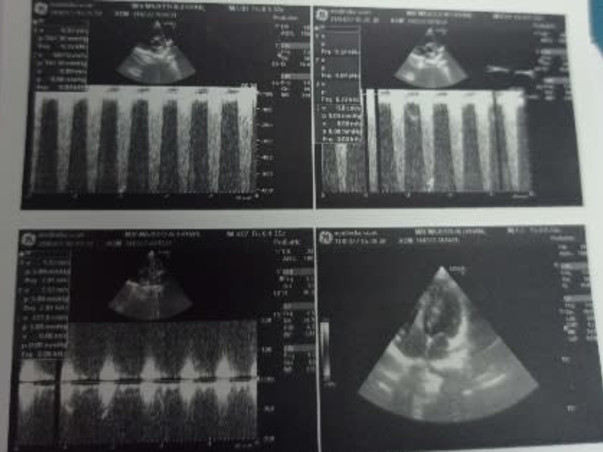

Mir Majid Ali Khan Is Suffering From A Cardiac Valve. From More Than A Year. He Is Receiving Other In Olive Hospital But Has Not Yet Been Admitted.